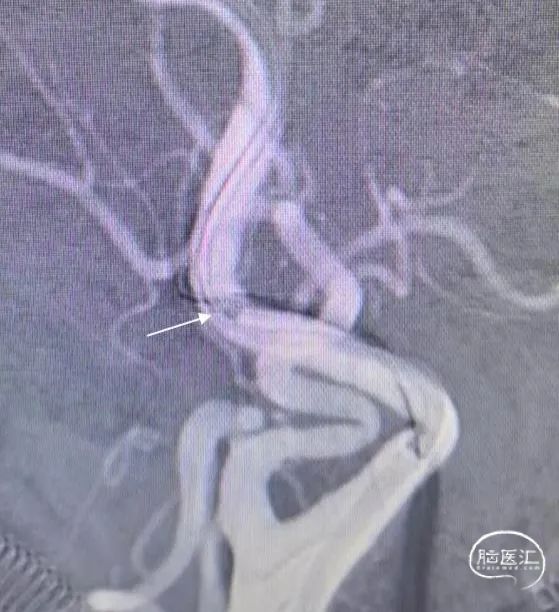

长鞘跟过颈内动脉起始部弯曲段后,在持续负压抽吸下,微导管微导丝顺利辅助抽吸导管通过海绵窦段至闭塞段以远接触血栓(红色箭头所示为导管头端,白色长箭头所示为路图下闭塞段;白色短箭头为长鞘位置)。

不减影图像中长鞘(白色箭头)和抽吸导管(红色箭头)位

侧位:抽吸导管到位、接触抽吸过程。

其一,抽吸导管接触血栓核心。栓子堵塞血管后,近端血流淤滞、发生假性闭塞形成继发血栓。这种假性闭塞在颈内动脉末端闭塞累及眼动脉时更明显,表现为颈内动脉颅外段全程显影受限,会被误认为颈动脉夹层或颈内动脉起始部狭窄病变。因此路图下的闭塞段非真正血栓核心,采用ADAPT技术取栓时,抽吸导管需要越过路图下的闭塞段接触远端血栓核心才能提高一次取栓成功率。一般操作为:当抽吸导管到达路图下闭塞段时开启负压抽吸、回撤微导管微导丝时顺势前跟抽吸导管接触血栓核心;持续接触90秒后缓慢回撤抽吸导管,观察有无回血。